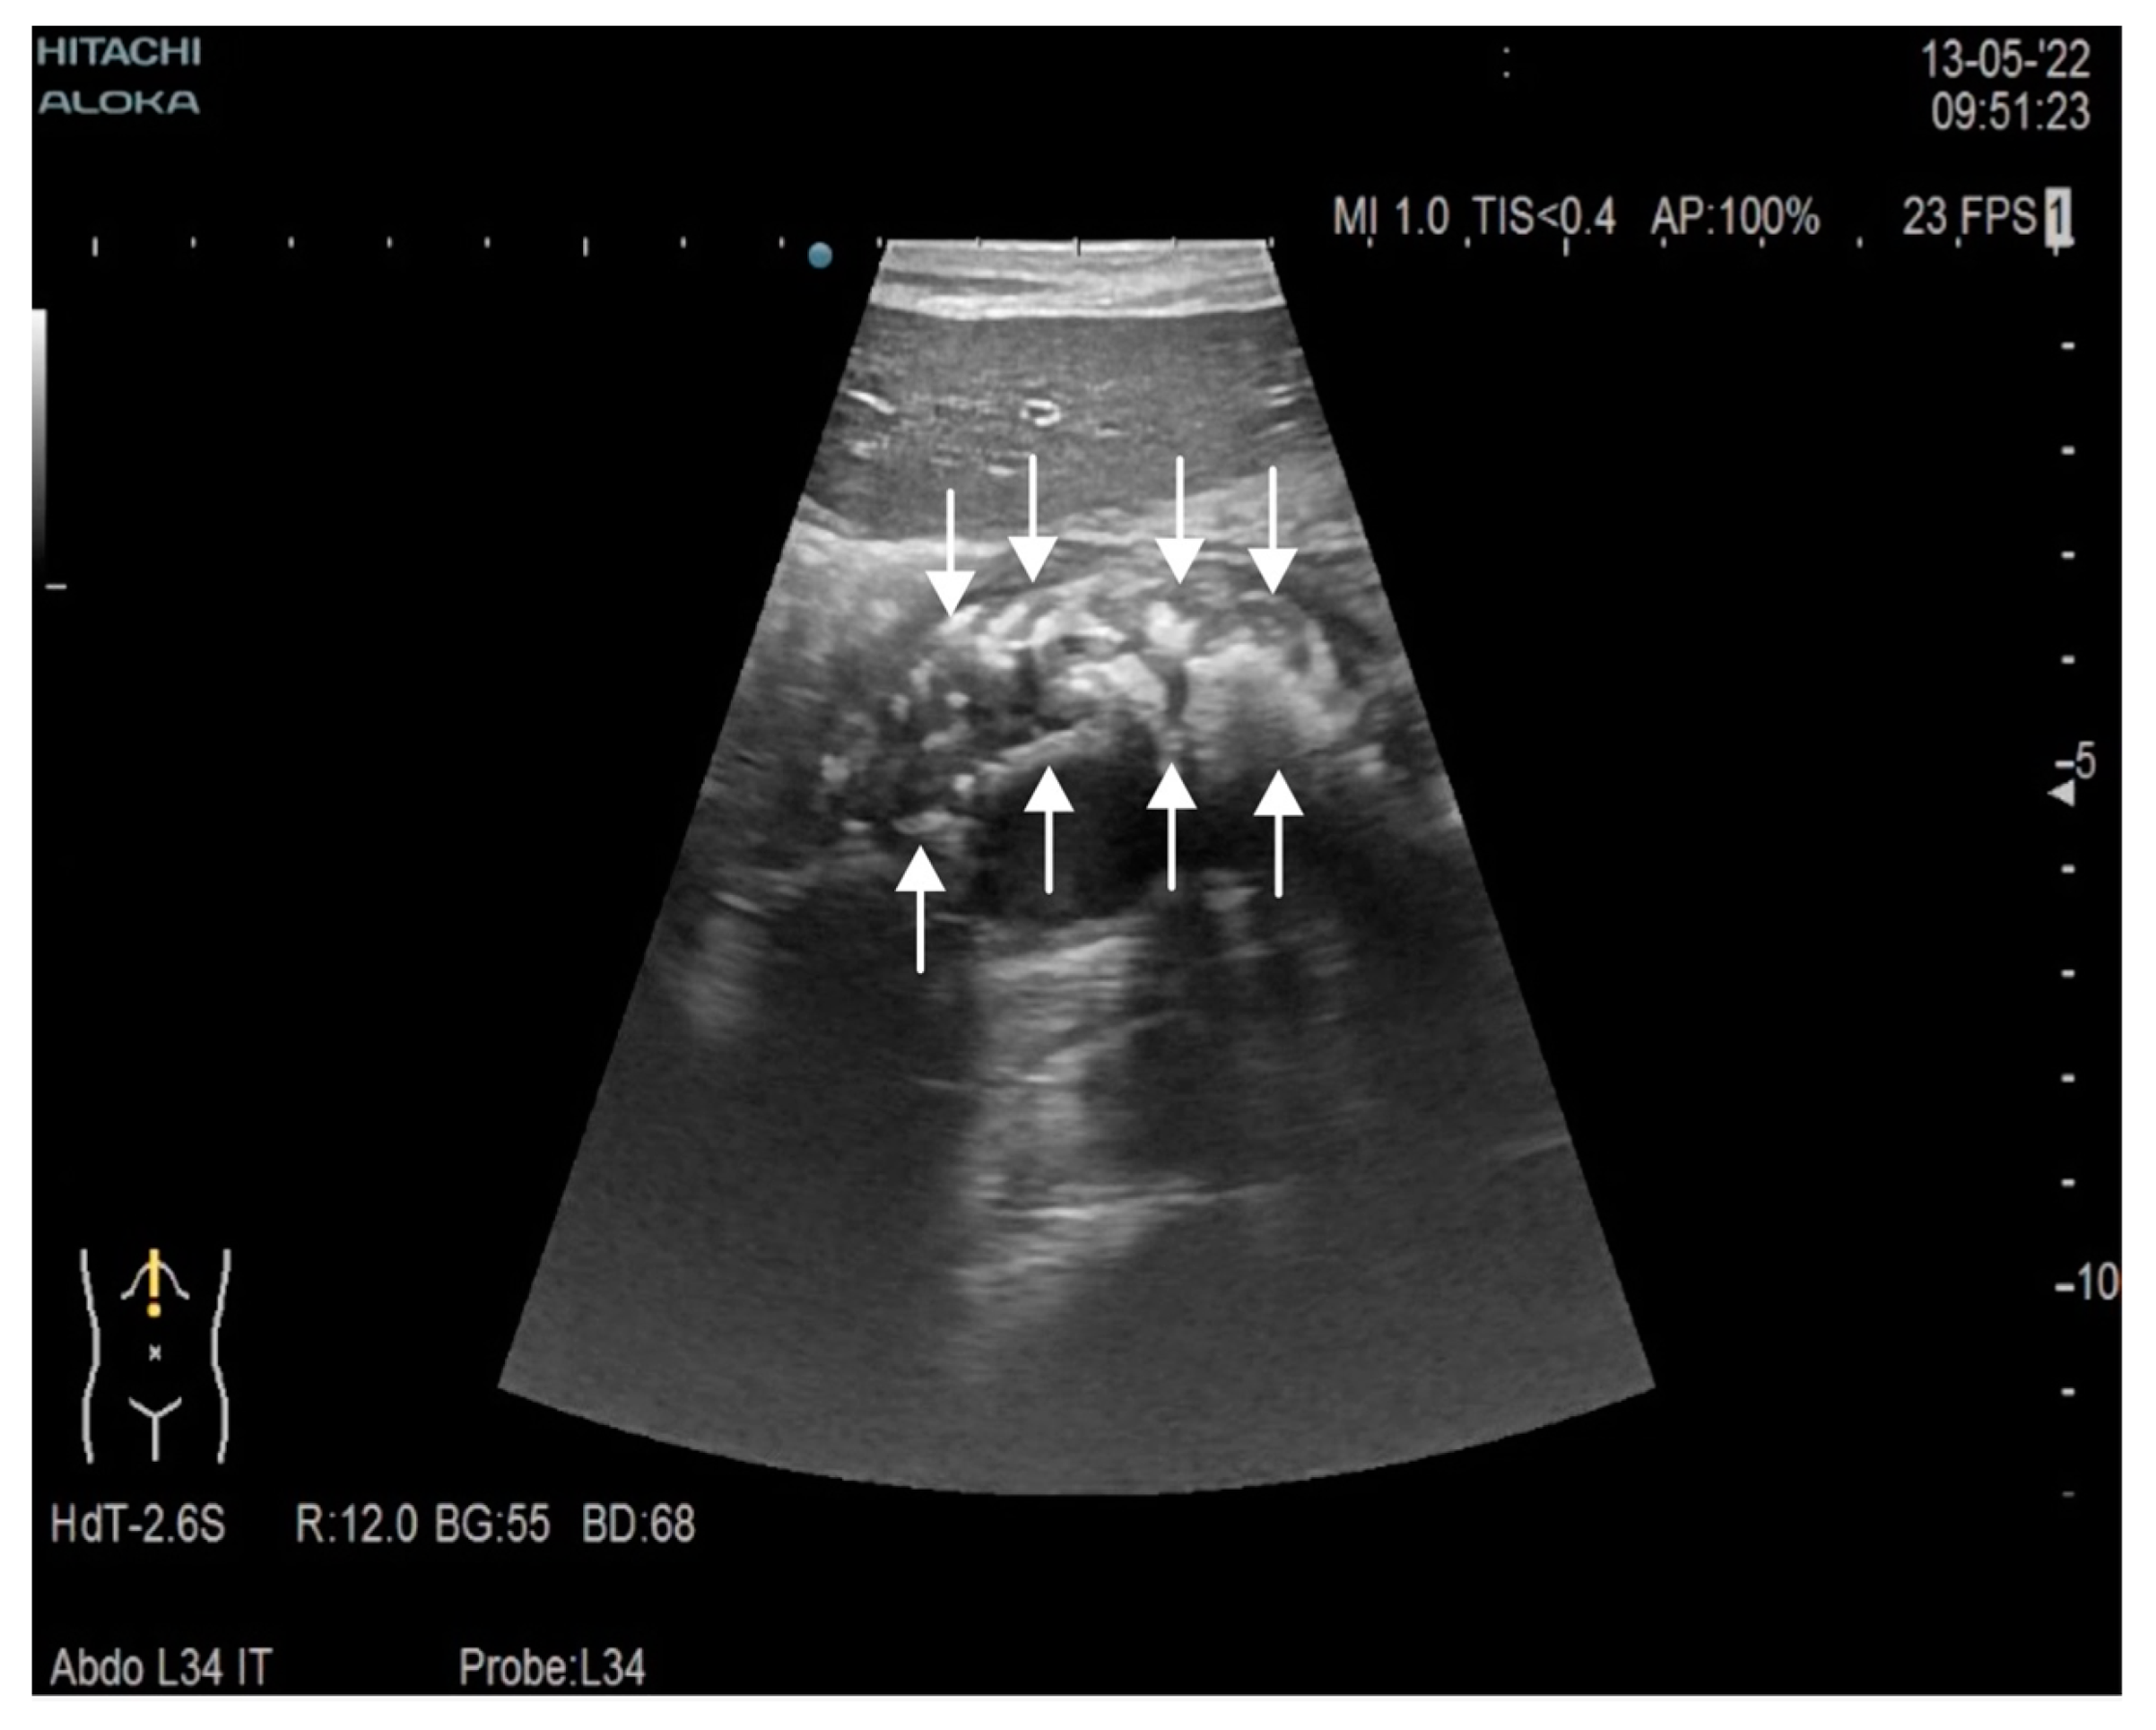

Chronic Calcifying Pancreatitis Associated with Secondary Diabetes Mellitus and Hepatosplenic Abscesses in a Young Male Patient: A Case Report

2. Case Report